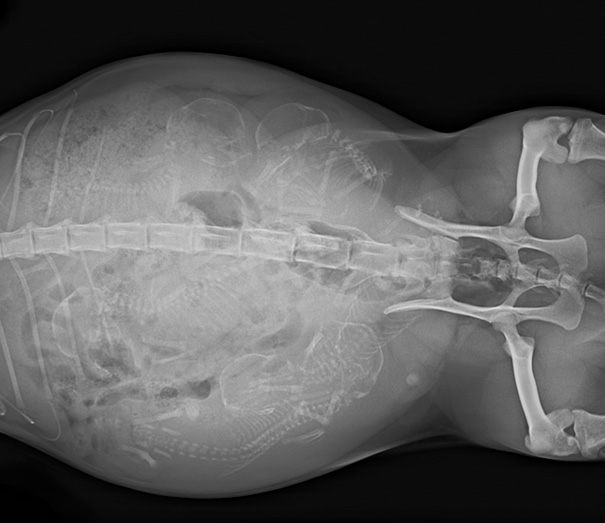

Pregnant Cat X-Ray

I don't know in this post, but sometimes they X-ray to make sure everything is ok or to make sure all the babies are out.

Load More Replies...The amount of babies that cats have just seems so shocking for their size.